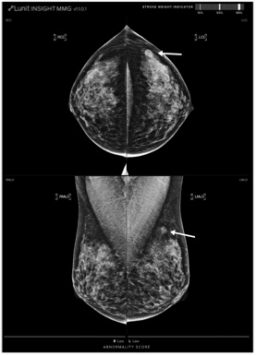

圖 一位44歲的患者被診斷為左乳有一個(gè)20毫米大小的三陰性亞型浸潤(rùn)性導(dǎo)管癌,分期為T1cN0。左側(cè)乳腺癌在1點(diǎn)鐘方向表現(xiàn)為腫塊(箭頭),被AI-CAD遺漏(異常評(píng)分7分)